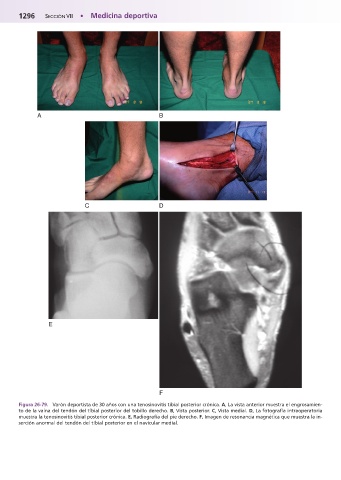

Figura 26-79.mVarón deportista de 30 años con una tenosinovitis tibial posterior crónica. A, La vista anterior muestra el engrosamien-

to de la vaina del tendón del tibial posterior del tobillo derecho. B, Vista posterior. C, Vista medial. D, La fotografía intraoperatoria

muestra la tenosinovitis tibial posterior crónica. E, Radiografía del pie derecho. F, Imagen de resonancia magnética que muestra la in-

serción anormal del tendón del tibial posterior en el navicular medial.